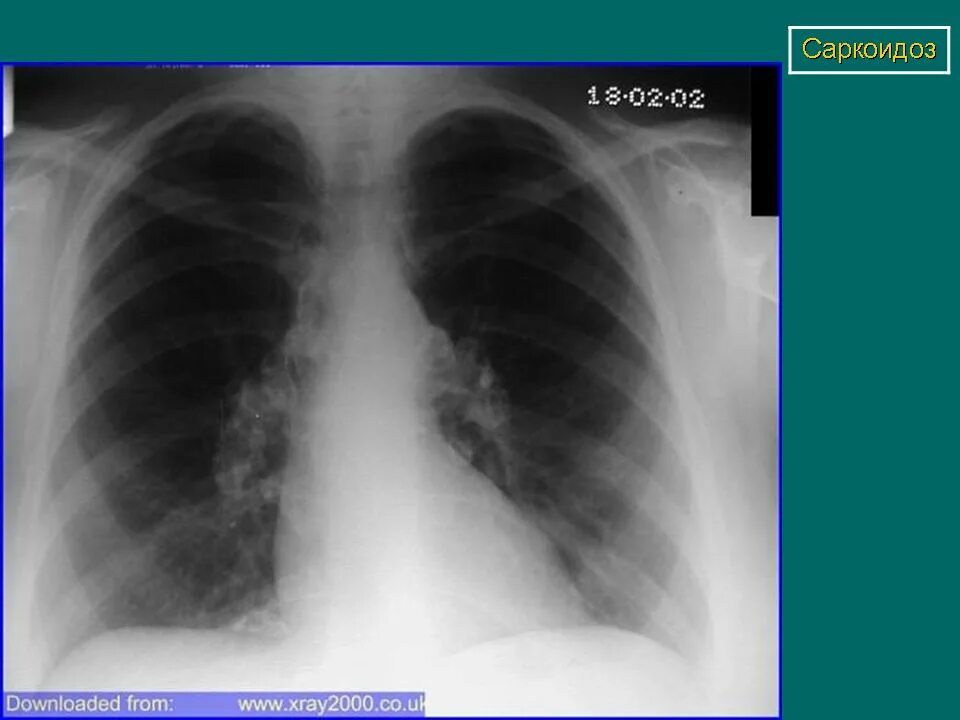

Саркоидоз код по мкб 10 у взрослых